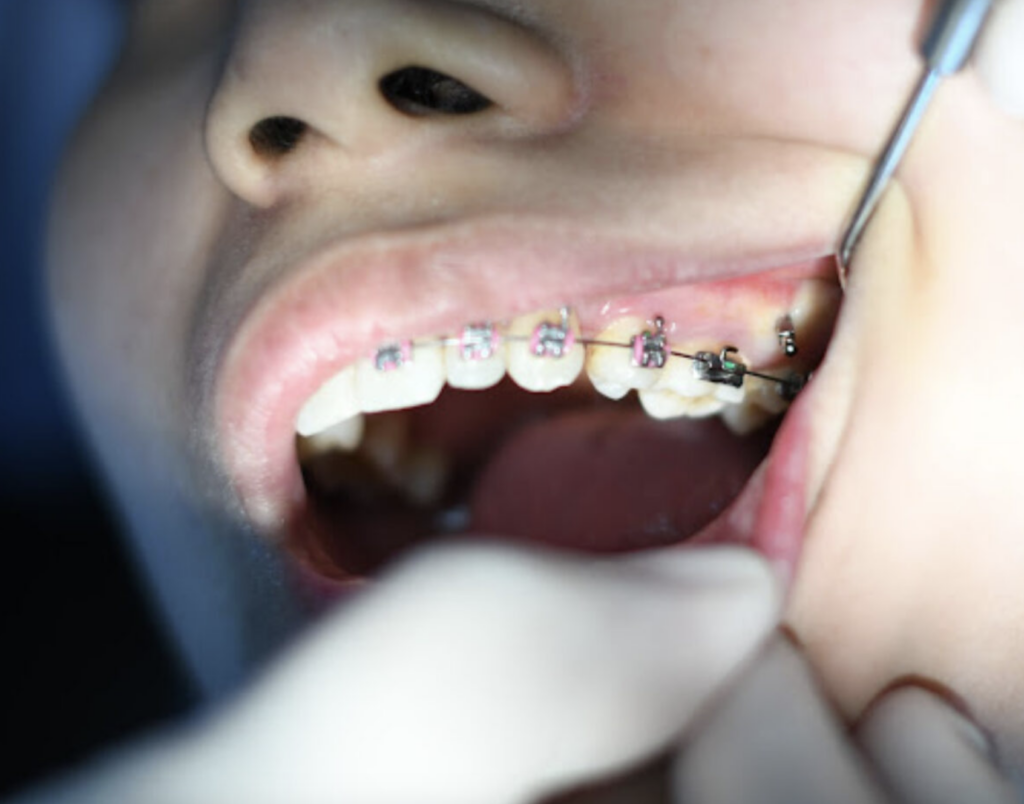

- Pencabutan gigi mungkin diperlukan sebelum rawatan brek gigi (braces) bagi gigi yang bertindak lapisan (dalam kes tertentu).

Sebelum prosedur pencabutan gigi dimulakan, doktor gigi anda akan menjalankan pemeriksaan terhadap gusi di sekeliling gigi yang akan dicabut.

- Terlebih dahulu, doktor gigi akan memberikan bius topikal kepada tisu gusi yang mengelilingi gigi yang akan dicabut. Gigi anda akan dilepaskan dengan lembut dan dikeluarkan dengan berhati-hati dari soketnya menggunakan alat-alat pergigian khusus.

- Bergantung kepada keadaan gigi, doktor gigi anda mungkin perlu membuat sayatan pada gusi untuk mencapai gigi yang reput atau patah pada garis gusi. Selepas gigi dicabut, soket akan dibersihkan dan disterilkan.